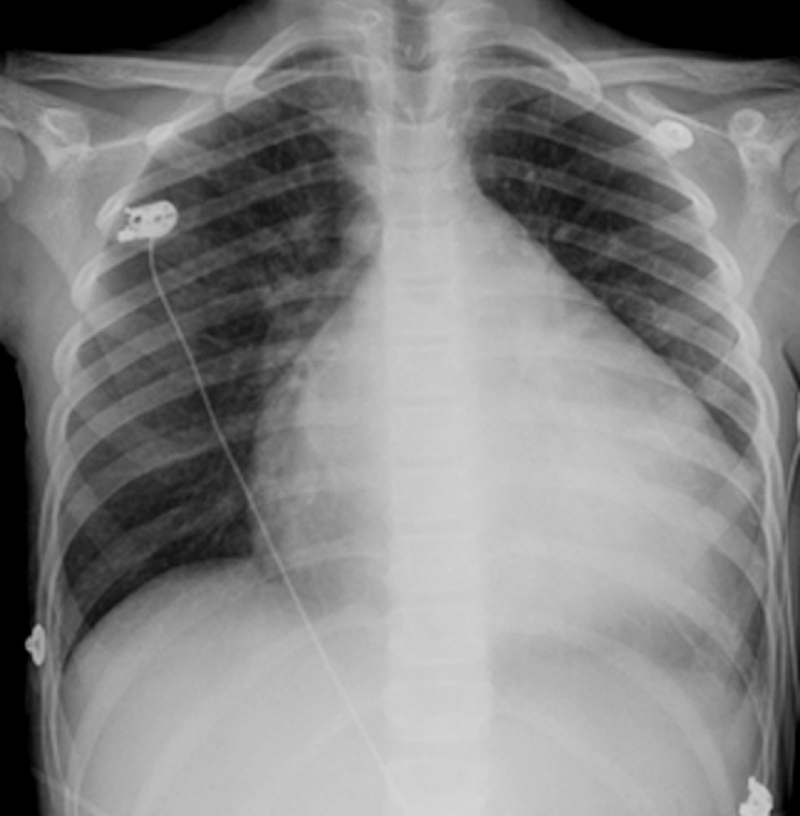

방사선촬영은 X선을 통해 이미지를 얻는 방법이다.

X선 발견 초기에는 일부 물질들을 제외하고 투과성이 높은 특성을 이용하여 좀처럼 보기 어려웠던 인체 내부를 투사해 의료용으로 사용하였고, 이 용도는 오늘날까지 이어지게 된다. X선을 주로 다루는 의학 분야는 영상의학과이다.

지금부터 유방암 검사 엑스레이를 찍으면 가슴 모양이 어떻게 찍히는지 함께 살펴보도록 하자.